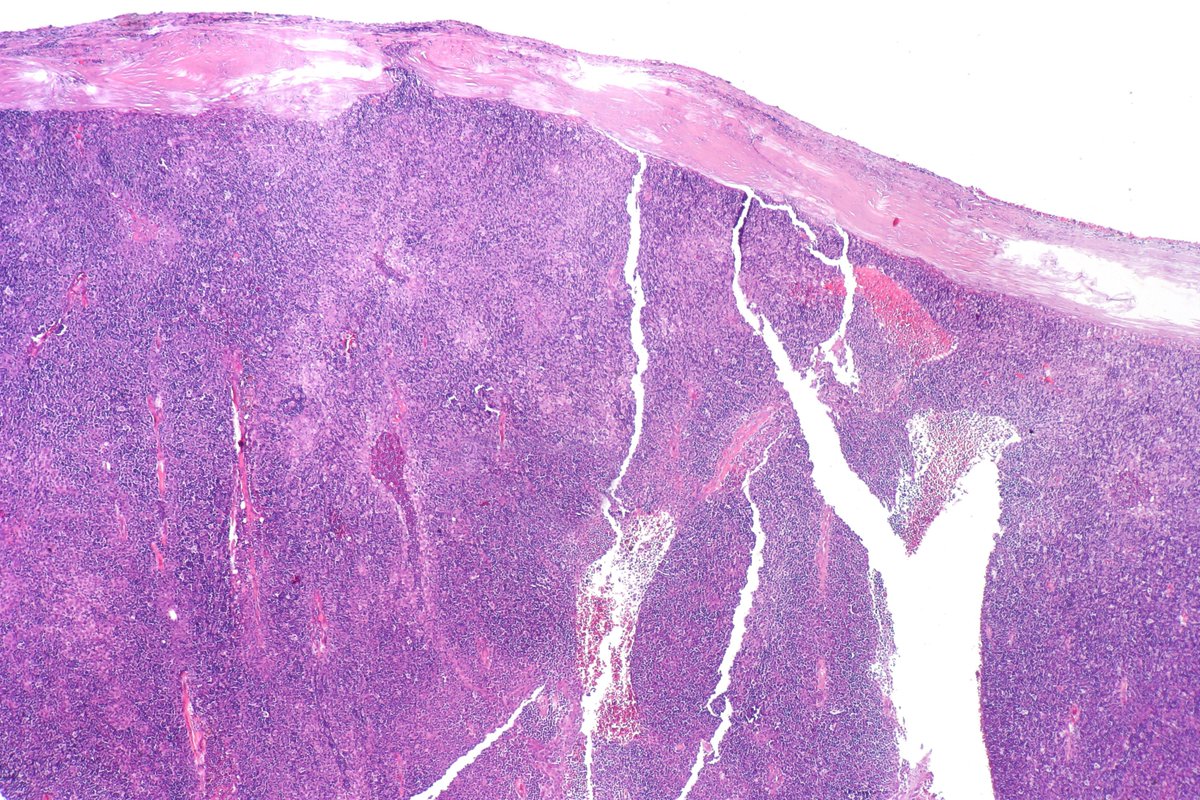

Type B2 Thymoma showing prominent large epithelial cells admixed with numerous lymphocytes. #pathology #PulmPath